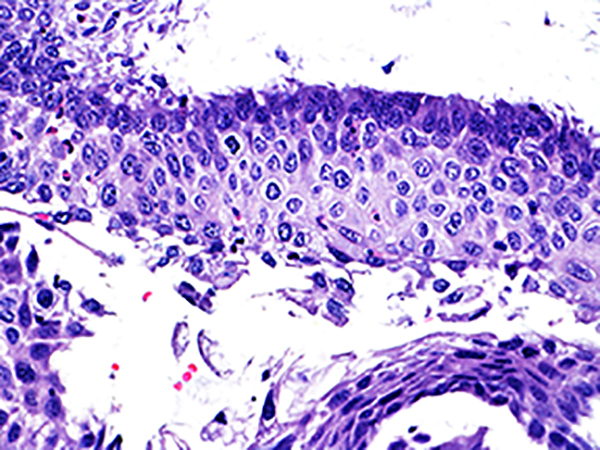

Case 1

Area 2 - Soft Bx CIN 2 40x - High Power |